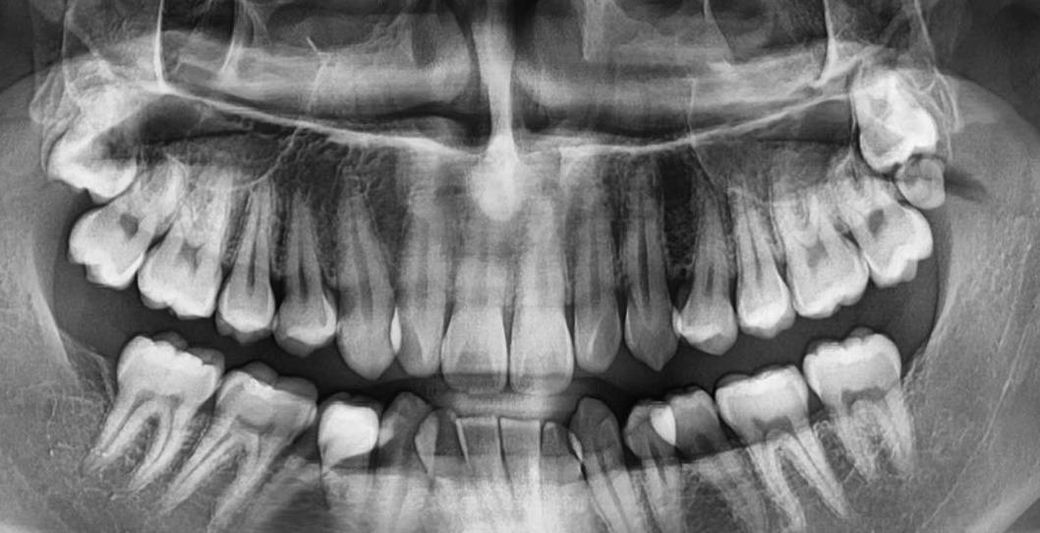

상악 매복 사랑니 발치 궁금합니다..

현재 위쪽에 양쪽으로 사랑니가 매복해있습니다. 교정을 진행하려면 매복 사랑니 발치는 필수적인가요? 그리고 상당이 위쪽에 깊게 박힌 것 같은데 발치 한다면 난이도나 통증은 어느 정도로 보시나요? 그리고 천공도 발생할 가능성이 큰 경우인가요??

• 1번 째 사진

사랑니가 매복되어 있고 따로 문제를 발생시키지 않는다면 발치를 할 필요는 없습니다. 치아를 후방으로 많이 이동해야 되는 상황이 있다면 발치를 해야 할 수도 있습니다.

1. 사랑니 발치가 무조건적인건 아니고 교정 시 필요한 공간이 얼마인지에 따라 다릅니다

2. 뼈에 파묻혀 있어서 난이도가 꽤 높습니다. 다만 마취가 잘 되면 통증은 걱정할 거 없습니다.

3. 천공 가능성 있습니다

저정도 매복사랑니라면 교정시 발치를 무조건 하실필요는 없을것같습니다. 일단은 교정 진단을 먼저 받아보세요.